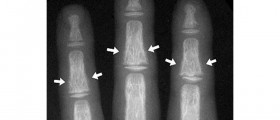

Renal Osteodystrophy

Bone disorder Although, the term “renal” points to a disease related to kidneys, renal osteodystrophy is in fact a bone disorder that occurs when kidneys fail to maintain the proper levels of calcium and phosphorus in blood.